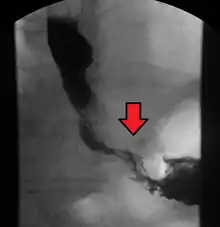

Although an occlusive tumor may be suspected on a barium swallow or barium meal, the diagnosis is best made with an examination using an endoscope. This involves the passing of a flexible tube with a light and camera down the esophagus and examining the wall, and is called an esophagogastroduodenoscopy. Biopsies taken of suspicious lesions are then examined histologically for signs of malignancy.

Additional testing is needed to assess how much the cancer has spread (see § Staging, below). Computed tomography (CT) of the chest, abdomen and pelvis can evaluate whether the cancer has spread to adjacent tissues or distant organs (especially liver and lymph nodes). The sensitivity of a CT scan is limited by its ability to detect masses (e.g. enlarged lymph nodes or involved organs) generally larger than 1 cm.[43][44] Positron emission tomography is also used to estimate the extent of the disease and is regarded as more precise than CT alone.[45] PET/MR as a novel modality has shown promising results in preoperative staging with fair feasibility and good correlation in comparison to PET/CT. It can enhance tissue differentiation with lowering the radiation dose to the patient.[46] Esophageal endoscopic ultrasound can provide staging information regarding the level of tumor invasion, and possible spread to regional lymph nodes.

Contrast CT scan showing an esophageal tumor (axial view)

Contrast CT scan showing an esophageal tumor (coronal view)